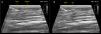

En nuestra práctica clínica siempre utilizamos guía ecográfica para asegurar el éxito del procedimiento y evitar complicaciones, en algunos casos usamos electroestimulación en forma simultánea (Figura 4).

Ecografía de apoyo al procedimiento de infiltración muscular con TB-A

A) Se muestra la trayectoria de la aguja en el músculo recto femoral. (Imagen de procedimiento de las autoras, con el apoyo ecográfico de Servicio de radiología Clínica Las Condes). B) Se muestra la trayectoria de la aguja y la inyección de TB-A en el músculo recto femoral. (Imagen de procedimiento de las autoras, con el apoyo ecográfico de Servicio de radiología Clínica Las Condes).